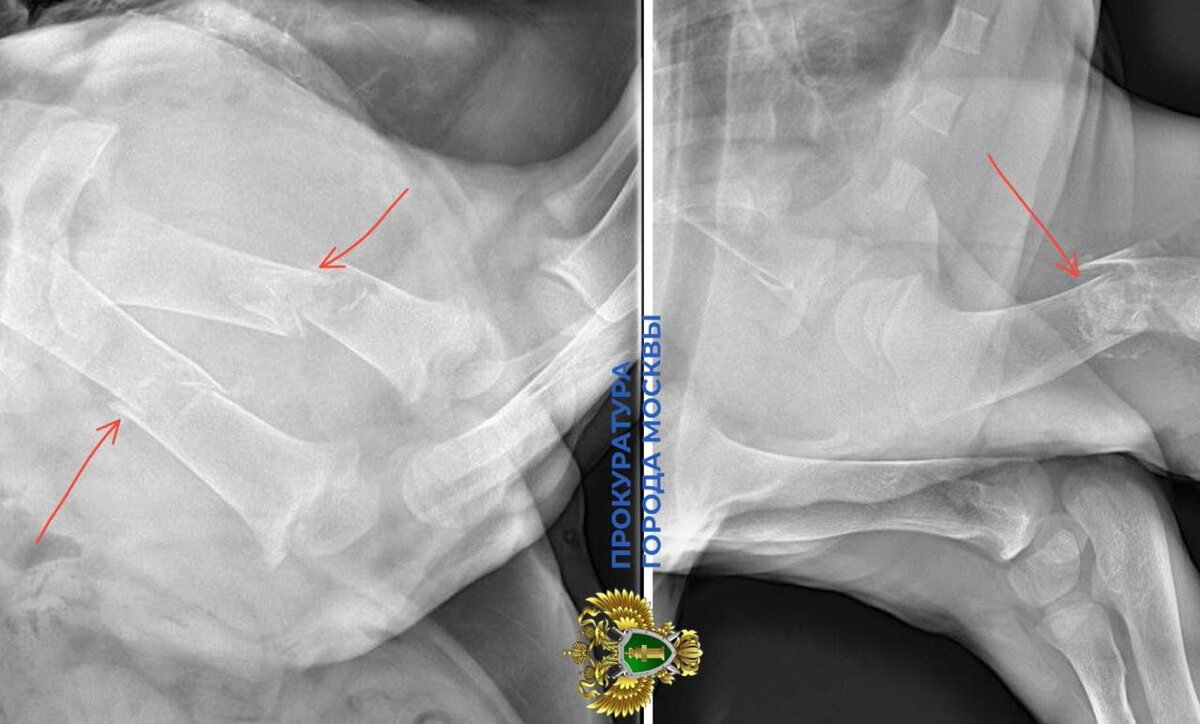

В ночь на 25 декабря специалистам передали маленькую львицу в критическом состоянии. У животного сломаны три лапы, повреждён позвоночник, отмечены последствия неправильного содержания и питания. Львёнок жил в качестве домашнего питомца в одной из квартир в Москва-Сити. Львы относятся к животным, запрещённым к частному содержанию. Проводится проверка законности приобретения и содержания, а также жестокого обращения с животным. По результатам при наличии оснований будут приняты меры прокурорского реагирования. В настоящее время львица проходит необходимое лечение и реабилитацию под присмотром специалистов. ПРОКУРАТУРА МОСКВЫ